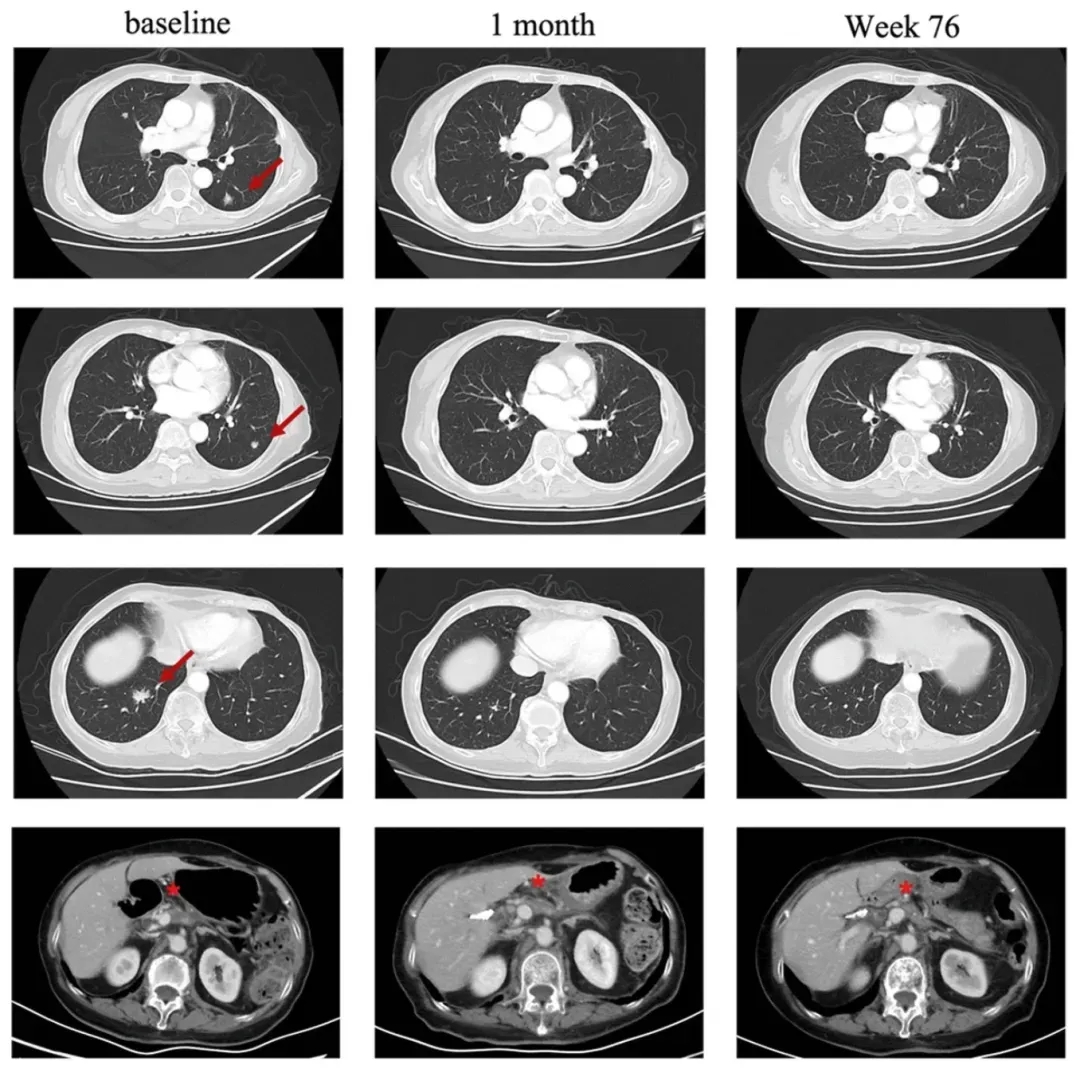

值得一提的是,一例62岁女性患者,已经出现肺部转移的胃腺癌,在接受CAR-T治疗后仅4周,肺部的1个靶病灶完全消失,另外2个病灶显著缩小(详见下图)。

令人惊喜的是,该患者在治疗后第4周,达到部分缓解(PR)。之后肺部靶病灶进一步消失,最终竟然幸运地获得了完全缓解(CR)!而且让医生倍感欣慰的是,截至末次随访时(2023年7月),该患者仍处于持续缓解状态。

图1 该患者在CT041治疗前后,肺部病变的放射学对比

注:“红色箭头”表示目标病变;“★”表示原发病变。